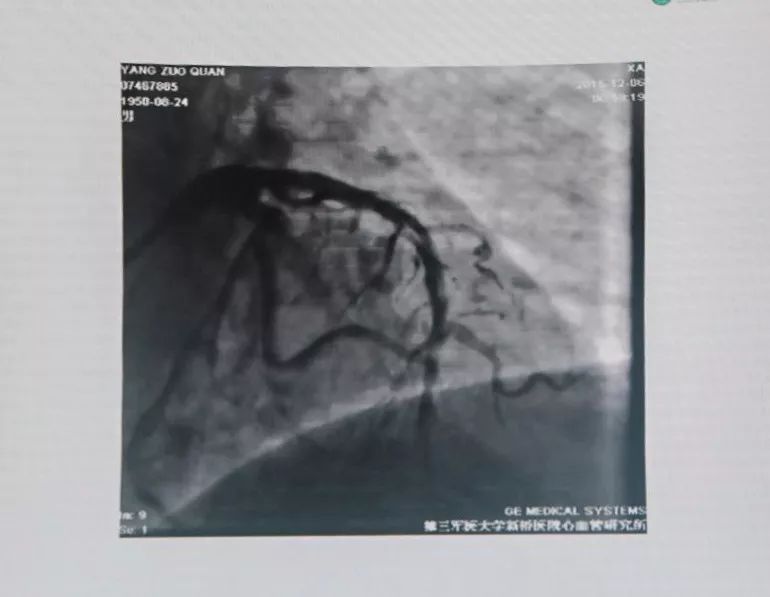

联系陆军军医大学第二附属医院胸痛中心,考虑亚急性支架内血栓形成,绕行急诊,PPCI。

分析血栓形成原因,可能是患者术后自行停用DAPT,支架贴壁不良等。

有条件者应尽快进入导管室行急诊冠状动脉造影,以多体位投照明确无夹层及支架膨胀不良。若血管完全闭塞,待球囊扩张部分血流恢复后再行造影。应尽快使导丝通过血栓病变,建议应用软头导引导丝。

支架内血栓形成可能与支架未充分贴壁有关。可用短于支架长度的高压球囊再次PTCA。若造影确认血栓形成可能与支架近或远端内膜撕裂、支架未完全覆盖病变有关,可再次置入支架,观察20 min后,若患者胸痛缓解、血压及心电监测稳定、TIMI血流III级,可视为成功。但应关注,除非有证据显示血栓形成与上述因素相关,否则不可再次置入新支架。Dutch研究发现,首次出现支架血栓的患者,再次置入新支架,发生支架血栓的风险比未置入新支架的患者增加4.2倍。